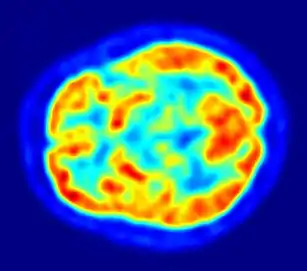

Важным направлением является медицинская физика, и её подобласти: ядерная медицина, радиотерапия и медицинская визуализация.[2] От рентгена до МРТ и ПЭТ: медицинская физика обеспечивает большую часть диагностических возможностей современной медицины наряду с предоставлением многих вариантов лечения.

Снимок с помощью ПЭТ